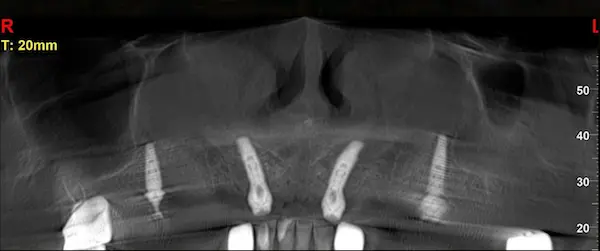

Сканы КТ имплантации зубов, 2026-04-18

Скан КТ, 2026-04-18

Сканы КТ имплантации зубов, 2026-04-18

Скан КТ имплантации зубов, 2026-04-17

Сканы КТ имплантации зубов, 2026-04-18

KT: имплантация зубов DentalKnysh, 2025-01-03, сканы

KT: имплантация зубов DentalKnysh, 2025-01-03, сканы

KT: имплантация зубов DentalKnysh, 2025-01-03, сканы

КТ имплантации зубов в DentalKnysh (10 имплантов), 2023-11-03

С 2023-09-05 по 2023-09-09 сканы КТ от 6 до 12 имплантов в DentalKnysh (4 фото):

Синуслифтинг и имплантация зубов, 6 имплантов, all-on-6, КТ скан 1, 2023-08-31

Фото отчет Имплантация зубов, 6 имплантов, КТ скан 3, 2023-08-31

Фото отчет Имплантация зубов, 8 имплантов, all-on-4, КТ скан 1, 2023-08-31